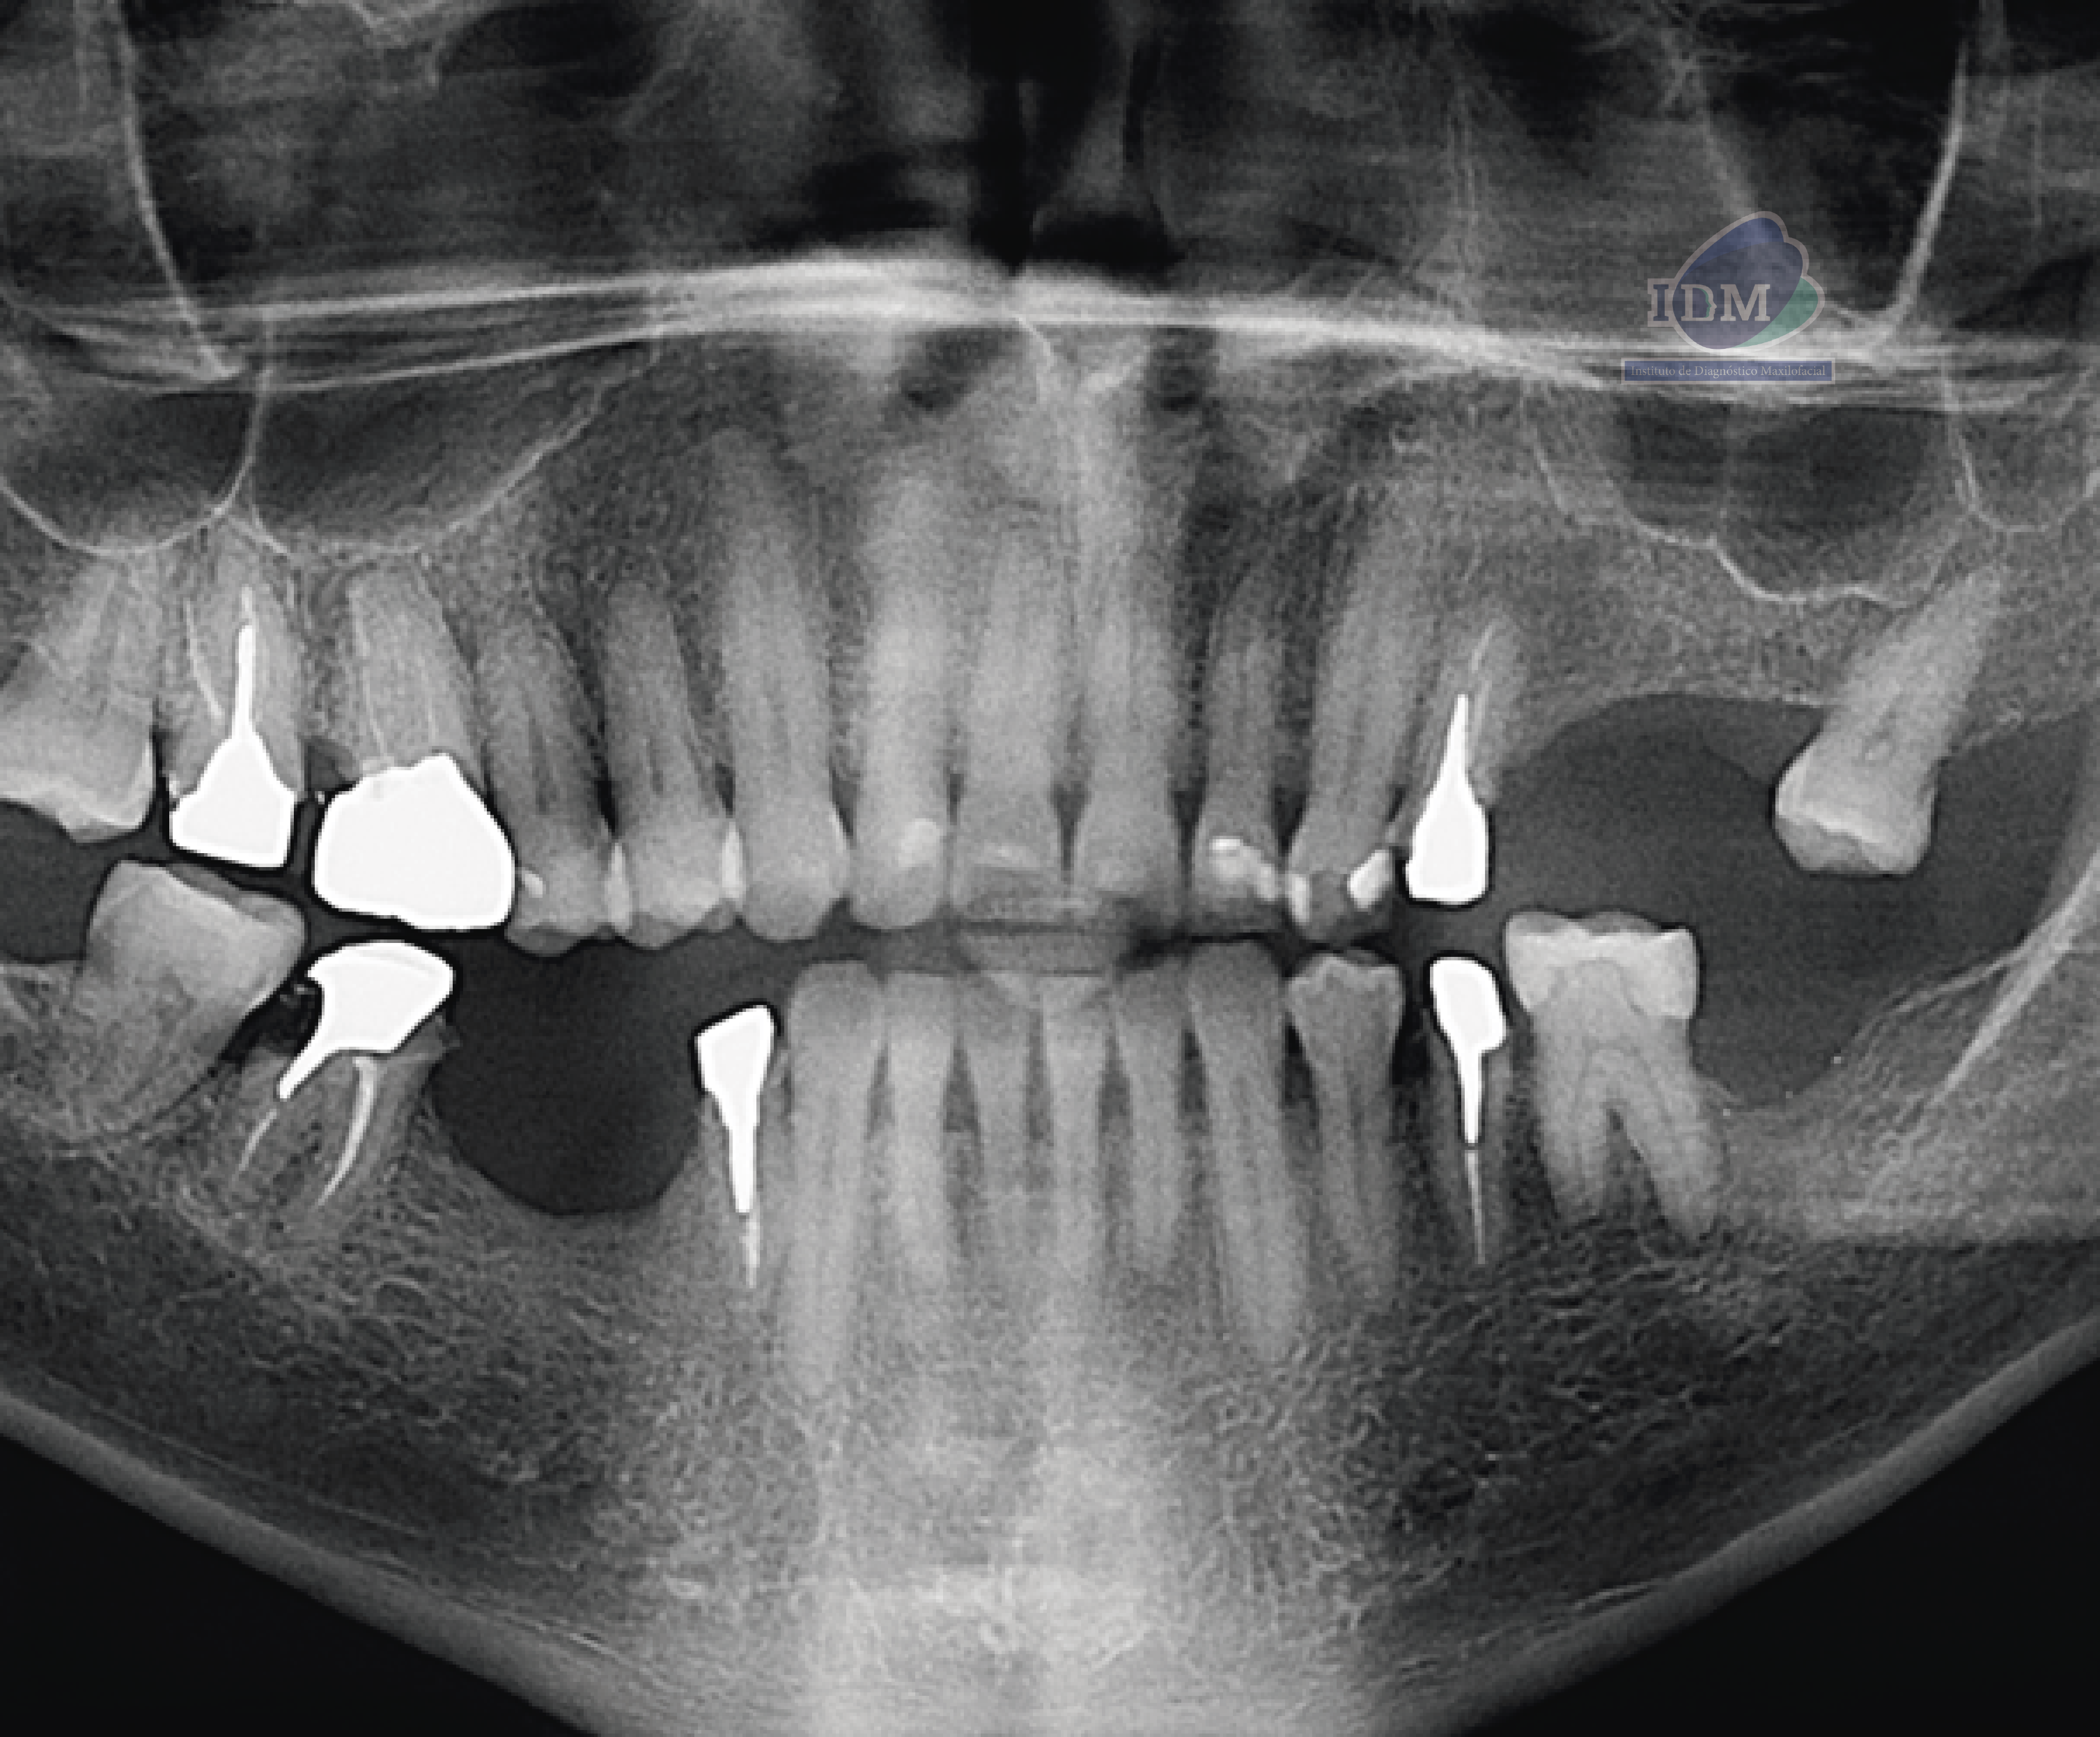

Radiografia Panorámica

En la radiografía panorámica se evidencia múltiples piezas dentarias con material restaurador y protésico, tratamientos de conductos en piezas 17,16,24,35,44,47 y lesión apical en pieza 16.

Si bien las radiografías panorámicas continúan siendo útiles como primera aproximación diagnóstica, presentan limitaciones importantes debido a la superposición de estructuras, la posible distorsión de la imagen o la orientación del foramen, que puede ocultar su presencia. En este caso, los múltiples agujeros mentonianos del lado izquierdo no fueron evidenciados en la radiografía panorámica. La tomografía computarizada de haz cónico permitió identificarlos con precisión, demostrando su valor como herramienta indispensable para el diagnóstico detallado y la planificación quirúrgica, especialmente en la colocación de implantes en esta región (2).